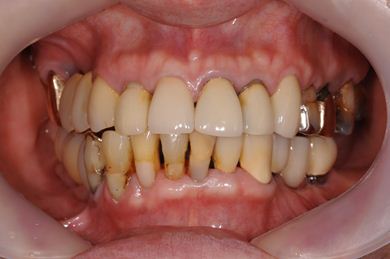

抜歯即日スピードインプラント治療+インプラント除去+セラミック治療

| 性別/年齢 | 女性 / 76歳 | ||||||||||||||||||||||||||||||||

| 主訴 | 20年前に入れたインプラントの周囲が腫れて気になっている。左下の一部治療後の歯が欠けている。 | ||||||||||||||||||||||||||||||||

| 治療内容 | インプラント5本(抜歯即日スピードインプラント)、ハイブリッドセラミック9本(セラミック用土台2本)、メタルボンドセラミック2本(メタルボンド用土台1本)、インプラント除去1本 | ||||||||||||||||||||||||||||||||

| 総治療費 | 2,514,645円 | ||||||||||||||||||||||||||||||||

| 治療期間 | 1年11ヶ月 |